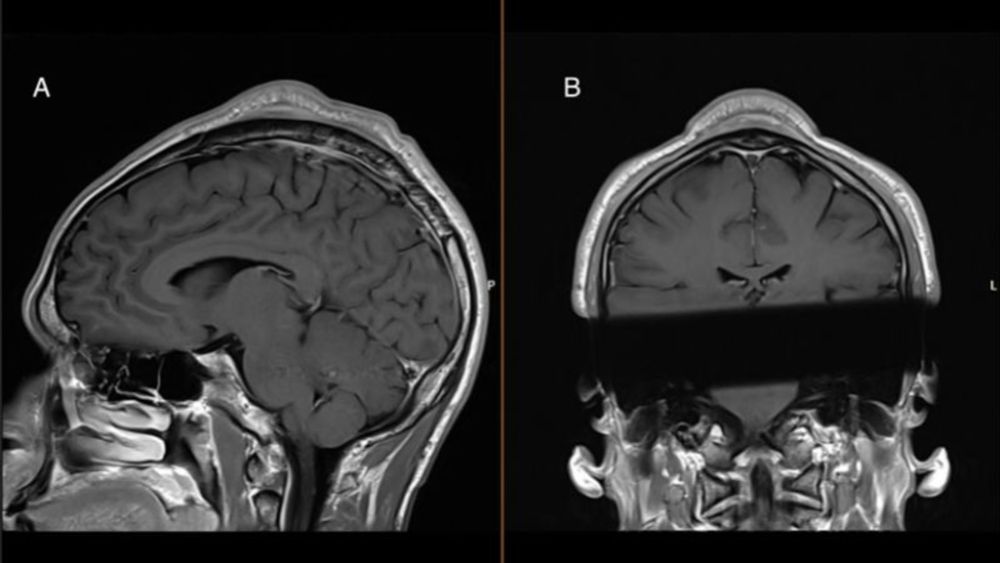

Hora de atualizar a Pokedex!

Vem no fio ver o que capturamos!

Hora de atualizar a Pokedex!

Vem no fio ver o que capturamos!